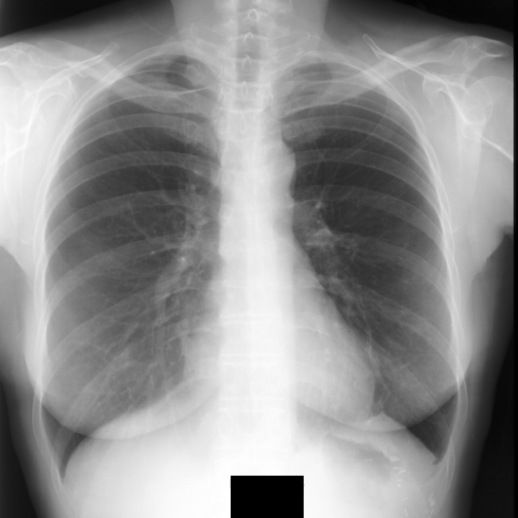

3.2.1 Performance in Chest Region Segmentation

We evaluate segmentation performance across six tasks spanning five datasets, all focused on chest anatomy (Tab. 4). Using a linear decoder, all X-ray–specific models outperform the general-domain DINOv2 baseline. Notably, XR-0 achieves the best performance on the JSRT dataset and ranks second across all other tasks. This strong performance is particularly noteworthy given that XR-0 is trained entirely from scratch—without warm-start initialization—and uses a relatively modest dataset ( 380K images, including 220K frontal chest X-rays), in contrast to chest-specific models like RadDINO. These results highlight the effectiveness of multi-anatomy pretraining in enabling robust generalization across anatomy-specific tasks.

However, when evaluated with the UPerNet decoder (Fig. 3, CXR-0 and XR-0 under-perform relative to DINOv2 and RadDINO. We hypothesize that this discrepancy stems from differences in intermediate feature quality. DINOv2, pretrained on large-scale natural images, consistently delivers top segmentation results, while RadDINO inherits these robust features via warm-start initialization. In contrast, our models are trained from scratch, which may limit the expressiveness of intermediate representations required by complex decoders like UPerNet.

The ability of XR-0 to perform competitively with a simple linear decoder highlights its potential for deployment in resource-constrained settings. The observed architectural trade-offs further emphasize the need to align decoder complexity with the quality of learned representations for optimal performance.

| PTX | VinDr-RibCXR | VinDr-RibCXR | SIIM-ACR | JSRT | PAX-Ray++ | ||

| Models | Decoder | private | instance | semantic | PTX | ||

| DINOv2 | Linear | 30.8 | 38.7 | 73.1 | 27.8 | 82.8 | 50.0 |

| RadDINO | Linear | 38.6 | 49.9 | 73.8 | 37.0 | 86.1 | 59.3 |

| CXR-0 | Linear | 32.9 | 41.3 | 73.3 | 29.1 | 82.6 | 55.3 |

| XR-0 | Linear | 34.0 | 42.7 | 73.6 | 32.6 | 86.2 | 56.3 |

| DINOv2 | UPerNet | 62.7 | 74.5 | 87.5 | 53.5 | 95.6 | 71.8 |

| RadDINO | UPerNet | 61.4 | 73.9 | 87.4 | 53.8 | 95.6 | 71.8 |

| CXR-0 | UPerNet | 52.0 | 71.0 | 85.9 | 47.0 | 95.0 | 71.0 |

| XR-0 | UPerNet | 54.9 | 70.6 | 86.0 | 49.4 | 95.2 | 70.7 |